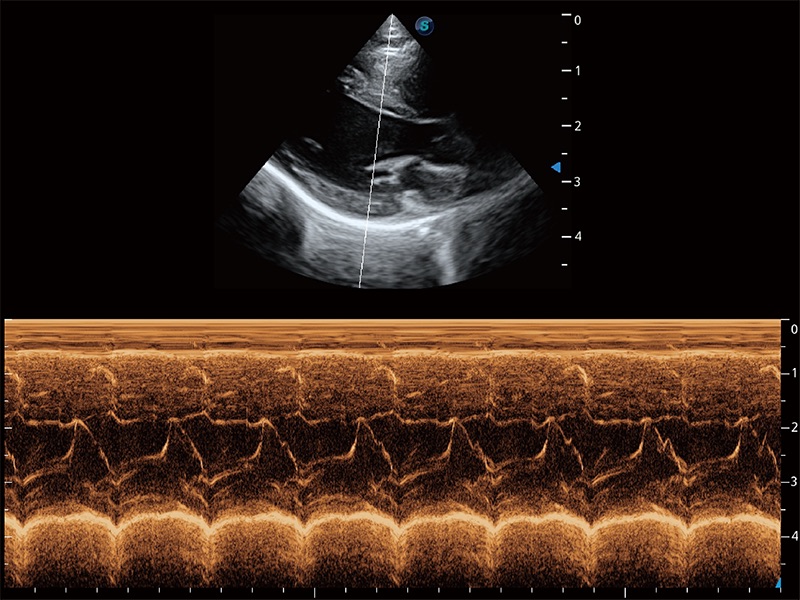

优异的基础图像

ProPet 80 全新的动物超声智能软件和丰富的探头群,为动物医生提供了高清晰度和精细分辨率的图像,无论在宠物、马科、畜牧还是实验室动物等应用中都可以轻松应对,为您的日常工作带来满意的体验。

(猫)二尖瓣M型